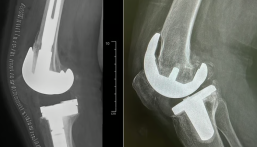

إنجاز جديد.. نجاح عملية استبدال مفصل الركبتين لمريضة في مجمع الدمام الطبي

في إنجاز طبي جديد، نجح فريق طبي في مجمع الدمام الطبي، أحد المرافق التابعة لشبكة الدمام الصحية، أحد مكونات تجمع الشرقية الصحي، في إجراء عملية استبدال مفصلي الركبتين لمريضة في عملية جراحية واحدة.

وحضرت المريضة إلى العيادات الخارجية وهي تعاني من آلام حادة، إضافة إلى صعوبة في أداء الأنشطة اليومية وتقييد ملحوظ في الحركة والمشي لمسافات قصيرة.

أوضح استشاري جراحة العظام في مجمع الدمام الطبي، الدكتور سعد الطاهر، أن الفريق الطبي قام بإجراء الفحوصات الإكلينيكية اللازمة، بما في ذلك الأشعة والتحاليل، للتأكد من حالة المريضة وتحديد إمكانية إجراء العملية في وقت واحد.